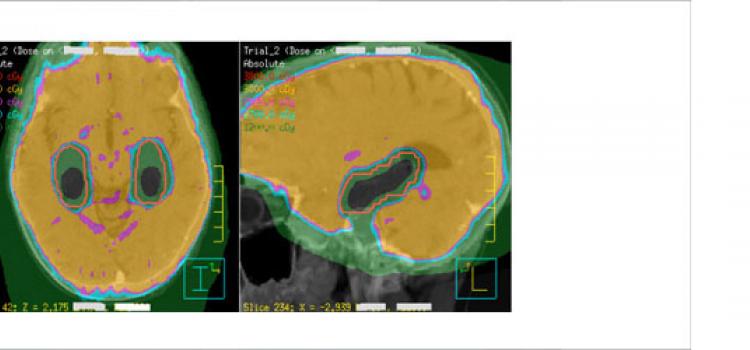

Brain metastases are 10 times more common than primary brain tumors, occurring in 10 to 20% of adult patients with cancer.1 The current limit of detection clinically is 2 to 5 mm in diameter, though metastases are more typically detected between 5 mm and 1 cm.2 Yet in their

Brain metastases are 10 times more common than primary brain tumors, occurring in 10 to 20% of adult patients with ...